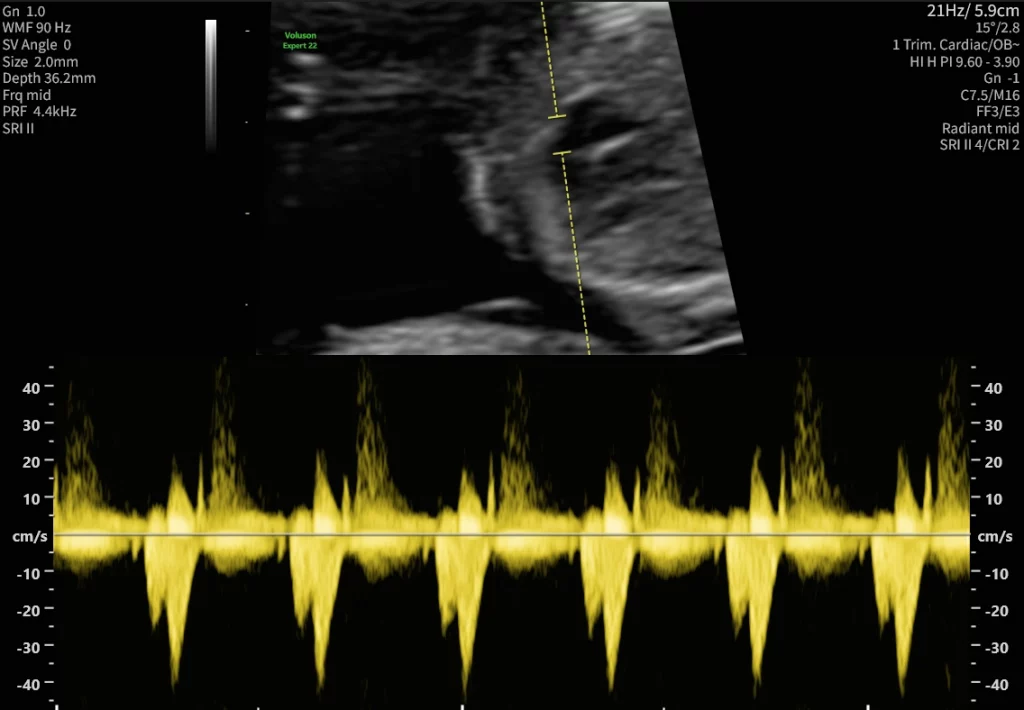

Das gesamte Kind wird genau angeschaut und ausgemessen, Organe wie Herz, Gehirn, das Knochengerüst, die inneren Organe und die Durchblutung werden überprüft.

Zusätzliche Kriterien sind die Messung des kindlichen Nasenbeins, Beurteilung des Blutflusses über den Herzklappen und Messung des venösen Blutflusses zum kindlichen Herzen hin. Parallel dazu können aus einer mütterlichen Blutprobe zwei Schwangerschaftshormone (freies ß-HCG und PAPP-A) analysiert werden. Besonders hohe oder niedrige Konzentrationen sind als Risiko für das mögliche Vorliegen von Chromosomenveränderungen und einer Reihe weiterer Erkrankungen zu werten. Aus den biochemischen Ergebnissen, den Ultraschalldaten und Ihren persönlichen Daten wird ein individuelles Risiko für Chromosomenstörungen in der vorliegenden Schwangerschaft errechnet.